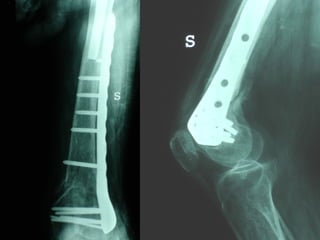

INDICAZIONI COMUNI Fratture sovracondiloidee Fratture intercondiliodee Fratture diafisarie distali PARTICOLARI Fratture con grave osteoporosi Fratture periprotesiche

VANTAGGI CHIRURGIA MININVASIVA Mini Open Inserimento della placca sottocutaneo per scivolamento Viti percutanee Preservazione dei tessuti molli Ridotto danno vascolare Rapida ripresa funzionale

F, 68 y

LISS  NCB

NCB

Conclusioni Riduzione  anatomica Minimo trauma chirurgico Corretto equilibrio fra elasticità e stabilità Precoce mobilizzazione